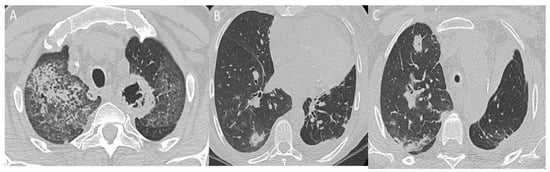

2.2. Pleural and Lung Parenchymal Involvement

- Nasser, M.; Cottin, V. Alveolar Hemorrhage in Vasculitis (Primary and Secondary). Semin Respir. Crit. Care Med. 2018, 39, 482–493. [Google Scholar] [CrossRef]

- Ceylan, N.; Bayraktaroglu, S.; Erturk, S.M.; Savas, R.; Alper, H. Pulmonary and Vascular Manifestations of Behcet Disease: Imaging Findings. AJR Am. J. Roentgenol. 2010, 194, W158–W164. [Google Scholar] [CrossRef]

- Chebbi, D.; Damak, C.; Frikha, F.; Abid, W.; Rebai, M.; Snoussi, M.; Salah, R.B.; Marzouk, S.; Hentati, A.; Bahloul, Z. Cavitary Lung Opacity of Unusual Cause during Behçet Disease. Clin. Cas. Rep. 2022, 10, e6173. [Google Scholar] [CrossRef] [PubMed]

- Schwarz, M.I. Rare diseases bullet 10: Small vessel vasculitis of the lung. Thorax 2000, 55, 502–510. [Google Scholar] [CrossRef] [PubMed]